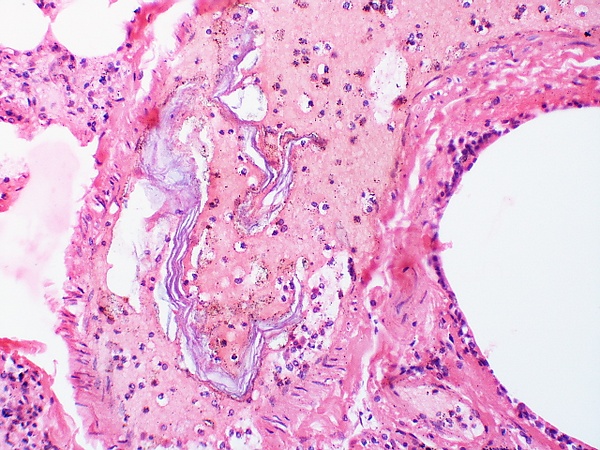

Патогенез ЭОВ связан с иммунологической реакцией на компоненты амниотической жидкости. Критическим условием для развития этого состояния служит градиент давления, при котором внутриматочное давление становится выше, чем в венах матки, способствуя проникновению околоплодных вод в материнский кровоток. Амниотическая жидкость представляет собой сложную биологическую среду, содержащую: мукопротеиды с большим количеством углеводов, белки, глюкозу, витамины, ферменты, микроэлементы, липиды, адреналин, норадреналин, тироксин, эстрадиол и другие стероидные гормоны, гистамин, нитросоединения, ПГ, роговые чешуйки, слизь, мекониальные частицы, волосы, сыровидную смазку. Кроме того, в ОВ есть вещества с высокой тромбопластиноподобной и антифибринолитической активностью, которые активируют прокоагулянтную систему, что ведёт к развитию ДВС-синдрома и распространённым тромбозам. ОВ вызывают механическую обструкцию мелких и крупных сосудов лёгких. Это приводит к нарушению перфузии лёгких, вазоконстрикции, повышению давления в лёгочной артерии, снижению сердечного выброса, правожелудочковой недостаточности[5].